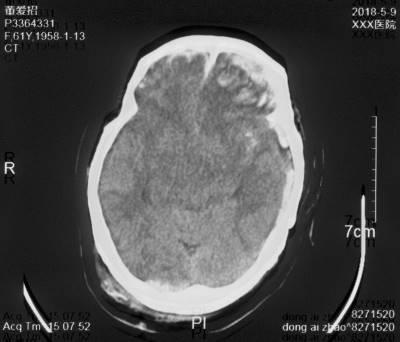

复阅2020年4月29日CT片:左侧额颞部颅骨修补、脑积水分流术后改变,人工颅板在位,双侧额颞叶、左侧枕叶及右侧小脑半球见片状低密度阴影,左侧脑室较右侧稍扩大,内见引流管在位。提示左侧额颞部颅骨修补、脑积水分流术后,双侧额颞叶、左侧枕叶及右侧小脑半球软化灶形成。

图13-15,2020年4月29日 CT片,左侧额颞部颅骨修补、脑积水分流术后,双侧额颞叶、左侧枕叶及右侧小脑半球软化灶形成。